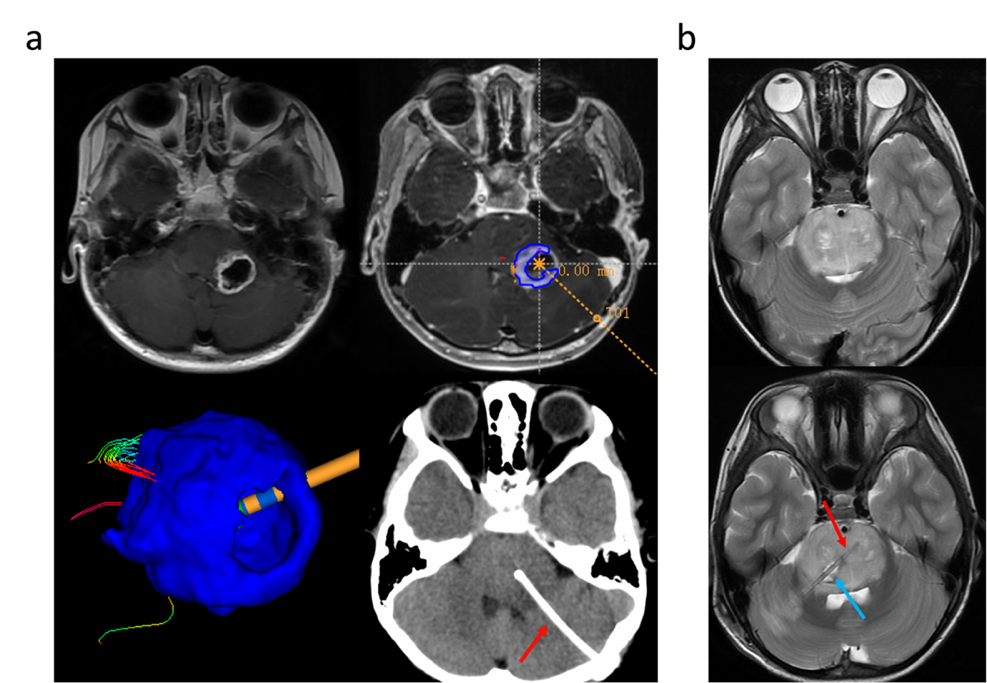

患者在入院后行头颅核磁共振检查,确定病灶的主体位置,并制定手术方案。使用 REME 机器人将头颅 CT 影像以及 MRI 影像进行融合,确定穿刺的路径,进行穿刺活检。活检后进行术中冰冻病理的检查,如果病理结果回报确定为高级别胶质瘤,则沿着活检通道进行 Ommaya 囊的植入(图 1)。

图 1:本图展示了 Ommaya 储液囊在脑干中的示意图位置以及病毒治疗后的 T2 磁共振代表影像